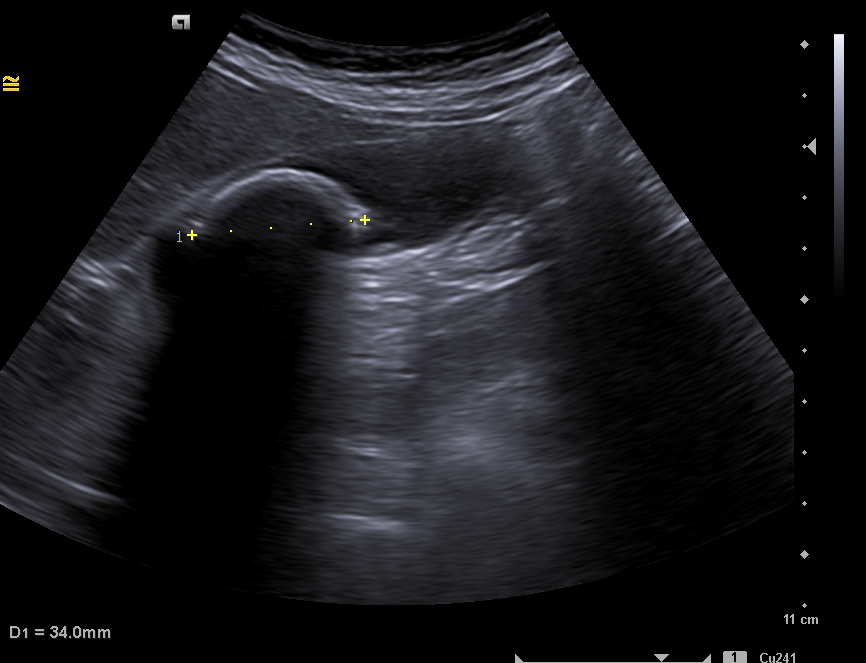

Ante la clínica se cita a la paciente en ayunas, para conseguir una máxima distensión de la vesícula.  Se observa una imagen hiperecogénica  móvil, con sombra acústica posterior compatible con litiasis de 35 mm. Sin colección perivesicular ni dilatación de la vía biliar intrahepática y extrahepática. Hígado con ecoestructura y ecogenicidad normal, sin LOES en su interior.  Hallazgos compatibles con litiasis vesicular gigante, descartando el diagnóstico de vesícula en porcelana.